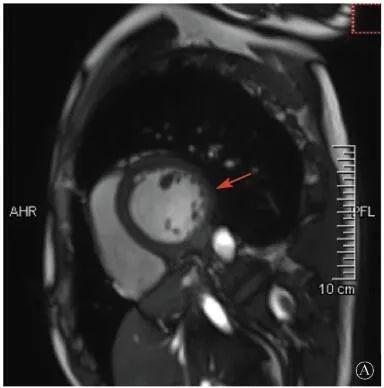

案例介紹:患者男性,20歲,因為"胸痛4個月,加重1月余"于2019年7月10日入院。患者2019年4月無明顯誘因出現(xiàn)心前區(qū)隱痛,VAS 3分,無放射,無胸悶、憋氣、活動后氣短,每月發(fā)作1~2次,未在意。同年5月體檢發(fā)現(xiàn),肌酸激酶(CK)2928 U/L、肌酸激酶MB質(zhì)量(CK-MB)46 U/L、心肌肌鈣蛋白I(cTnI)0.055 ng/ml。6月初,患者"感冒"后出現(xiàn)心前區(qū)疼痛加重,為過電樣疼痛,VAS 5分,無放射,持續(xù)約30~60 min可好轉(zhuǎn),胸痛每周約發(fā)作2次,否認呼吸困難、胸悶、心悸,否認活動耐量下降。6月8日,患者就診于外院查血生化:CK 1 215→1433 U/L,CK-MB 47 U/L,cTnI 30.17→31.79 ng/L;血脂(-);抗核抗體譜(-);超聲心動圖:左室增大,左室舒張末內(nèi)徑57 mm,左室射血分數(shù)39%,輕度二尖瓣關閉不全;磁共振心肌灌注延遲動態(tài)成像(圖1):左室稍增大,收縮功能稍減低;基底部至心尖部左室下壁及側(cè)壁、心尖部左室前壁心外膜下心肌纖維化,考慮非缺血性心肌?。患‰妶D:肌源性損害(偏慢性)。診斷"多發(fā)性肌炎、心肌損傷",予患者倍他樂克緩釋片23.75 mg/d、培哚普利0.5 mg/d、螺內(nèi)酯20 mg/d口服,患者未再出現(xiàn)心前區(qū)疼痛,但步行1 km左右會出現(xiàn)氣短、乏力。為進一步明確心力衰竭病因收入我院?;颊呱细咧衅鸪霈F(xiàn)體育課等劇烈活動后雙下肢明顯乏力,不能耐受1 km長跑類運動,日常體力活動不受影響,否認肌肉酸痛等不適。此次發(fā)病以來,一般情況尚可,否認尿量減少,體重無明顯變化。既往史:否認高血壓、冠心病、糖尿病病史。個人史:否認特殊毒物藥物接觸史,無煙酒嗜好?;橛贰⒓易迨罚何椿槲从?,否認家族類似病史,否認遺傳病史。入院查體:脈搏69次/min,血壓112/70 mmHg,指氧(自然狀態(tài))98%,體質(zhì)指數(shù)21.1 kg/m2;無皮疹;雙肺呼吸音清;心律齊,未聞及雜音;肝脾不大;雙側(cè)腓腸肌肥大,肌肉無壓痛;四肢肌力Ⅴ級、肌張力正常。雙下肢不腫。輔助檢查:入室床旁超聲心動圖提示左室壁運動普遍減低,心尖部、左室下后壁為著,肌小梁增多。

左室壁較廣泛心外膜下延遲強化,可見左室下后壁肌小梁增多(箭頭所示)

圖1 患者外院磁共振心肌灌注延遲動態(tài)成像